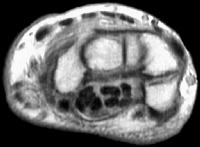

Sections through the carpal tunnel -  looking for a hook of hamate fracture or tendon discontinuity - were read as normal, although there may be a subtle signal irregularity through the hook of the hamate:

Is that a tendon rupture adjacent to the pisotriquetral joint?